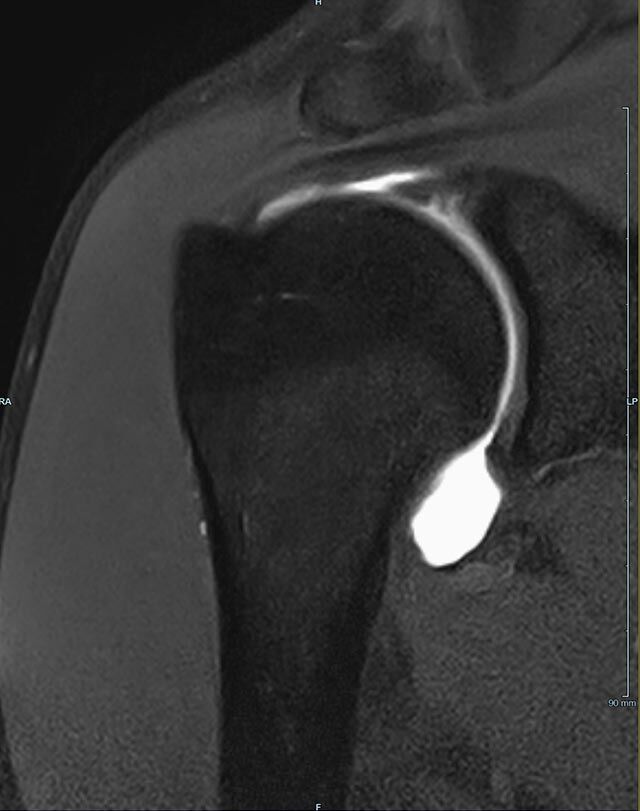

Gelenke

Arthrographie

• MR-Arthrographie – nach örtlicher Betäubung und gründlicher Desinfektion der Haut wird unter Lagekontrolle mit Röntgen-Durchleuchtung eine kleine Nadel in den Gelenkraum positoniert und darüber ein MR-taugliches Kontrastmittel in den Gelenkraum gespritzt. Danach wird die Nadel entfernt. Anschließend erfolgt die MRT des Gelenkes. Diese Methode stellt kleine anatomische Strukturen des Gelenkraumes verbessert dar, z.B. zur Therapieplanung vor Arthroskopie bei Sportverletzungen der Schulter oder Gelenkinstabilität.